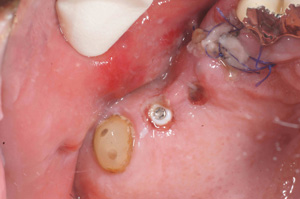

@A.Y.‚³‚ñ@31Î —«  ƒfƒUƒCƒi[@Žèp“ú@

‚Q‚O‚O‚W”N ‚TŒŽ‚P‚Q“úiŒŽj@‰ºŠ{

ƒm[ƒxƒ‹ƒKƒCƒhŽg—p

@@    ‰ºŠ{ ‚Q–{@”‚R‚UE”‚S‚U•”@’x‰„‰Ád

@   ”‚R‚U  Rpl Tapered Rp ‚SD‚Rmm ~ ‚P‚O mm@@@@”‚S‚U  Rpl Tapered Rp ‚SD‚Rmm ~ ‚P‚O mm